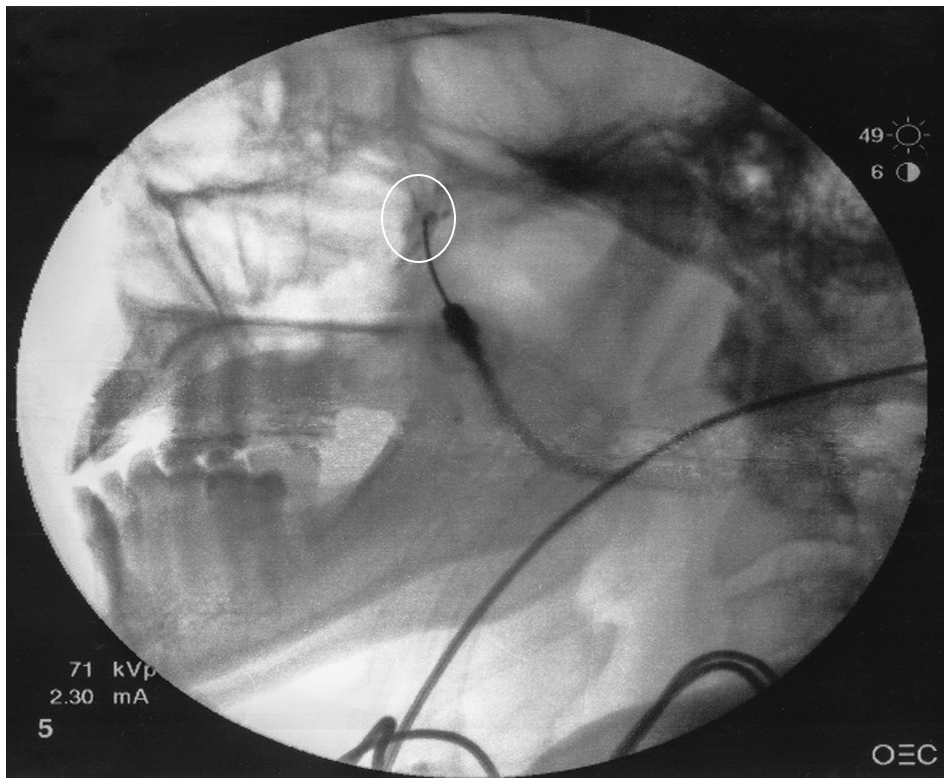

- Following final needle positioning, 0.2 mL of contrast material is injected under live fluoroscopic imaging to rule out intravascular spread and confirm spread of the dye within the pterygopalatine fossa (Figure 3).

Figure 3. Lateral view with contrast dye

White circle represents dye spread in the pterygopalatine fossa